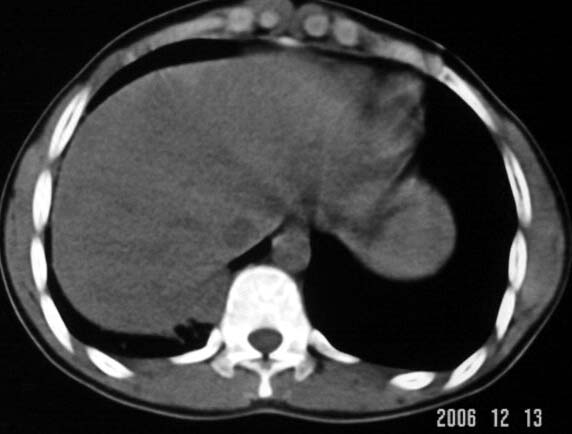

标题: CT5614:外伤病人男,20岁,右上腹痛.余肺野(-) [打印本页]

标题: CT5614:外伤病人男,20岁,右上腹痛.余肺野(-)

结合病史,应首先考虑右下肺挫裂伤,但也不能完全排除感染性病变。还需进一步询问临床症状!

外伤病人男,20岁,右上腹痛,ct显示:右肺下叶后基地段见斑片状高密度影,密度不均,边界清,考虑1,右肺下叶肺挫伤;2,炎症。